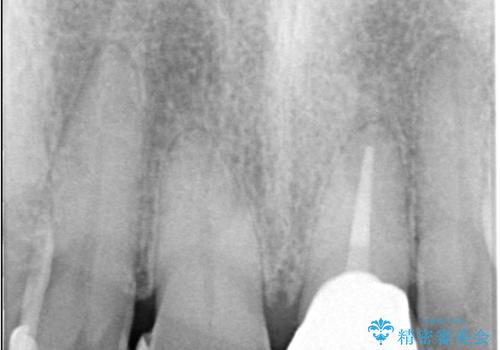

- 歯髄が死んで変色していた歯に対して、根管治療とオールセラミッククラウンでの修復を行いました。まず、根管治療で内部の感染を除去し、歯の強度を高めるためにファイバーコアを装着しました。その後、審美性と耐久性を考慮し、オールセラミッククラウンで覆うことで、自然な歯の色合いに近い美しい仕上がりを実現しました。

歯髄が死んだ歯は通常の健康な歯に比べて透過性が低く、特有の暗い色調を帯びる傾向にあります。変色は時間とともに進行し、薄い茶色や灰色、黄色がかった色合いになることが多いです。このような変色は、審美的な面で気になる場合が多く、オールセラミッククラウンなどでの修復が行われることも一般的です。